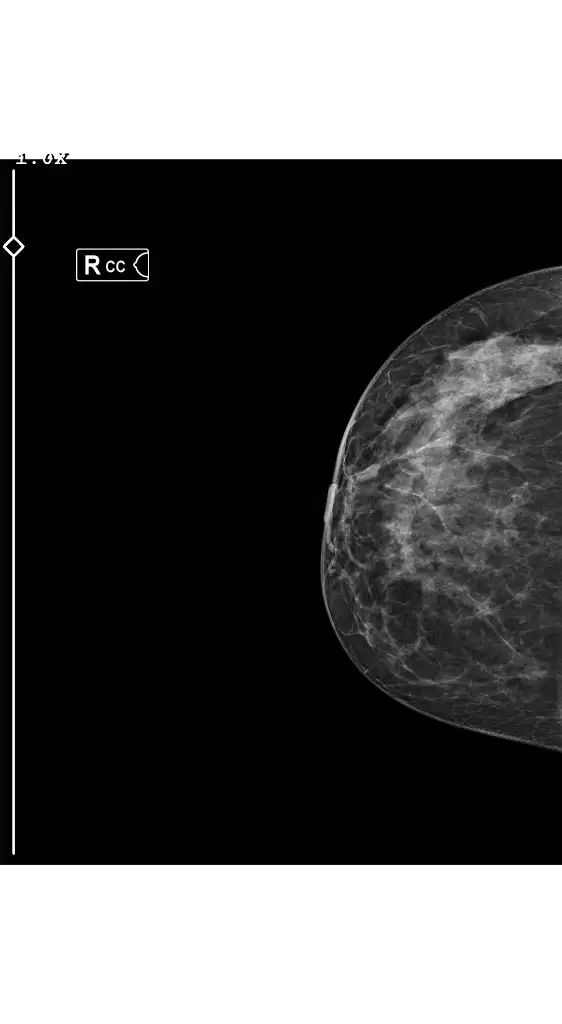

• 1000181882.webp

1000181882.webp

10,8 KB · Görüntüleme: 102